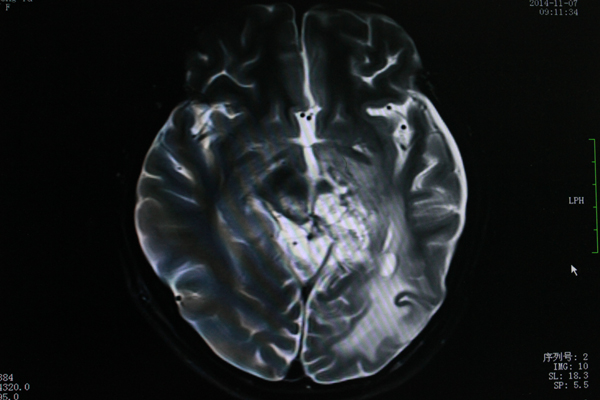

小雨9月MR图像

11月MR图像,可见肿瘤已明显缩小。